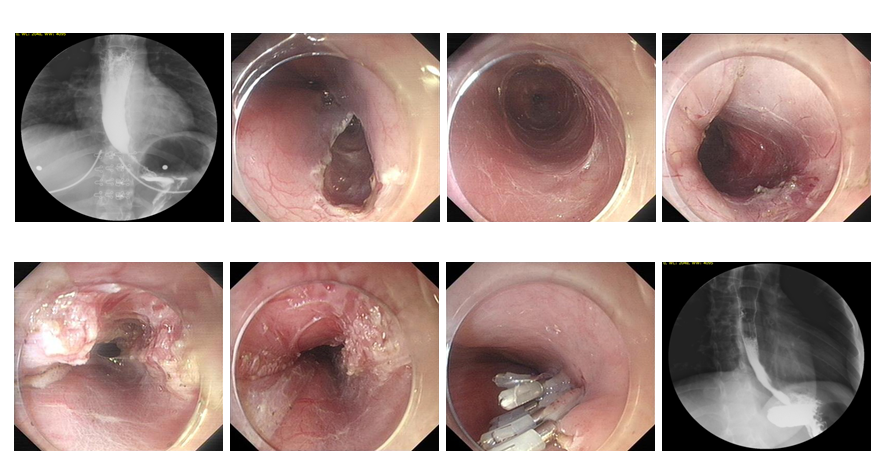

⑥ERCP

内镜下逆行胰胆管造影术(ERCP)指在内镜下经十二指肠乳头插管注入造影剂,做胆胰管X线造影胆汁细菌学和细胞学、胆道压力及乳头括约肌功能测定等检查,是公认的诊断胰胆管疾病的金标准。在ERCP的基础上可作十二指肠乳头括约肌切开术 、胆胰管碎石取石术 、胆胰管内支架安置引流术 、 鼻胆引流术及胆道蛔虫取出术等治疗。我院消化内科开展ERCP、EST等内镜 微创技术多年,至今已经完成多例胆道结石、蛔 虫、肿瘤、先天异常等疾病的的内镜诊疗,取得很好效果。

ERCP提示胆总管结石

切开乳头

取出结石

支架引流术

【内镜下十二指肠乳头括约肌切开取石术(EST)】

胆总管结石可引起急性化脓性胆管炎和急性胰腺炎,一旦诱发重症胆管炎或重症胰腺炎,死亡率很高,因此,该病应及时尽早治疗。胆总管结石的治疗方式很多,但以不开刀方式通过内镜经口腔进行取石—EST是目前最好的治疗方法。